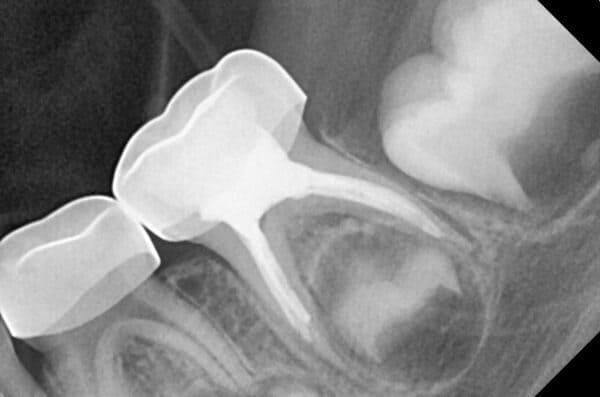

Система кореневих каналів молочних зубів часто складніша, ніж у постійних. Тому ми використовуємо ізоляцію робочого поля за допомогою кофердаму та спеціальне обладнання, щоб гарантувати високу якість лікування.

Важливо розуміти: це не швидка процедура. Вона вимагає ретельного очищення, промивання та пломбування каналів спеціальними матеріалами. Поспіх у цій справі може призвести до серйозних ускладнень у майбутньому.